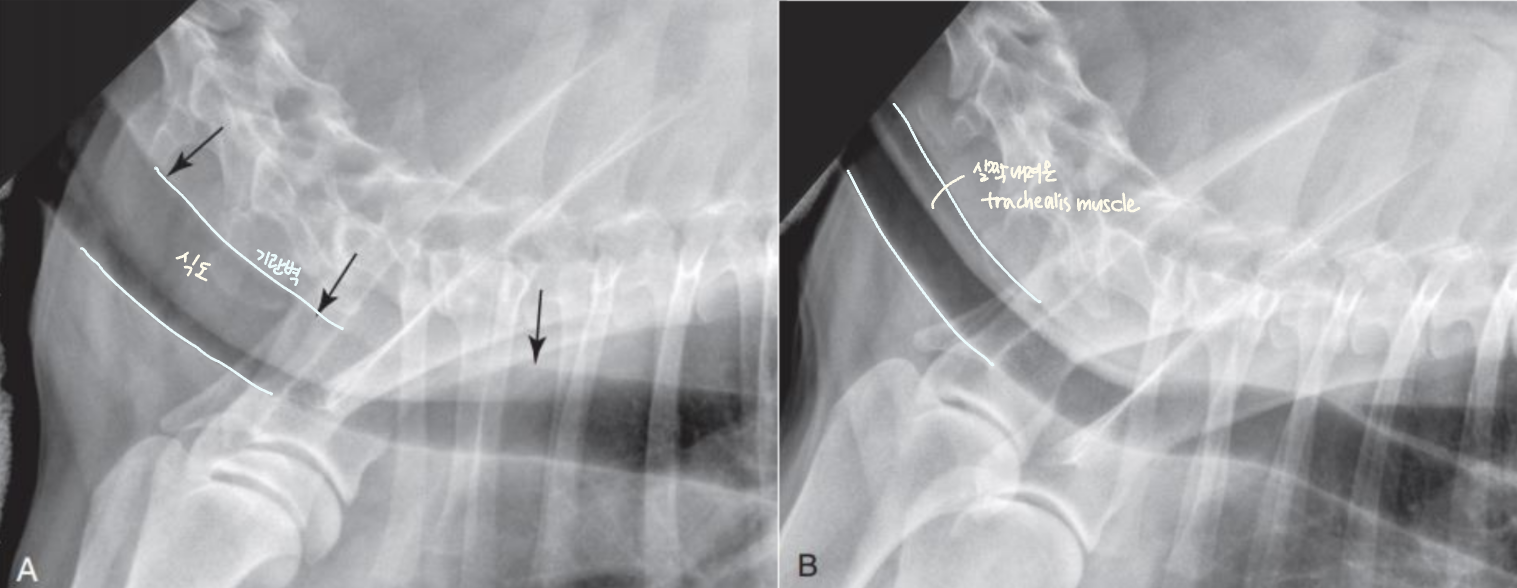

Tracheal Collapse (TC, ๊ธฐ๊ด ํํ)

| Tracheal collapse | |

| ์์ธ : ์ฃผ๋ก ์ฐ๊ณจ์ฐํ์ฆ(chondromalacia) ์ฆ์ : Goose-honking sound (grade 3 ์ด์์์) ์น๋ฃ : 1) ์ฒด์ค ๊ฐ๋ - 2) ์ฝ๋ฌผ - 3) stent ์ฅ์ฐฉ | ![]() |

| Static : ์ฃผ๊ธฐ ์๊ด์์ด ๊ณ์ ๋ฌด๋์ ธ ์์ Dynamic : ํธ๊ธฐ/ํก๊ธฐ์ ๋ฐ๋ผ ๋ฌ๋ผ์ง | |

| ๋ง์ด ๋ฌด๋์ง๋ ์์น Cervical : ํก๊ธฐ์๋ ๊ฒฝ์ถ ์ชฝ์ด ๋ง์ด ๋ฌด๋์ง (thoracic inlet) Intrathoracic : ํธ๊ธฐ์๋ ํ๊ฐ ์๋ ฅ์ด ์ฆ๊ฐํ์ฌ ํ๊ฐ ์ชฝ์ด ๋ฌด๋์ง | ![]() |